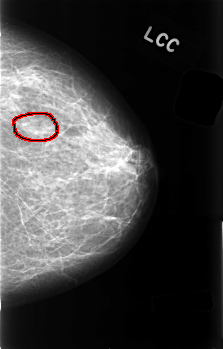

FILE: C_0489_1.LEFT_CC.OVERLAY

TOTAL_ABNORMALITIES 1

ABNORMALITY 1

LESION_TYPE MASS SHAPE OVAL MARGINS ILL_DEFINED

ASSESSMENT 3

SUBTLETY 4

PATHOLOGY BENIGN

TOTAL_OUTLINES 1

BOUNDARY